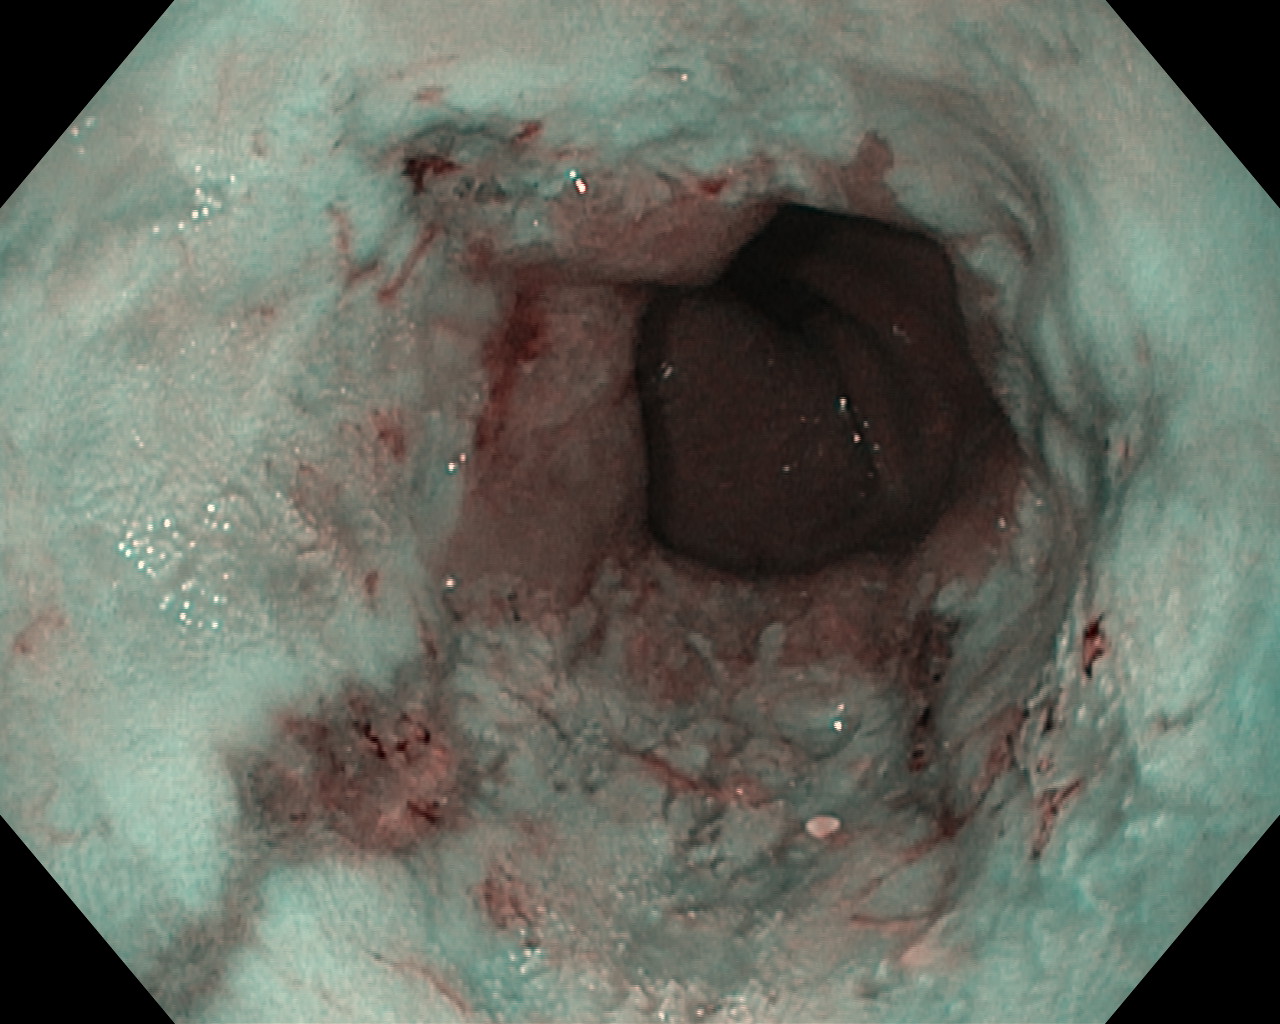

Obrazy endoskopowe

Choroba refluksowa